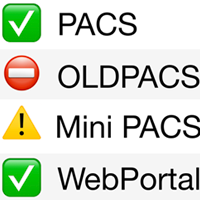

Optimised Engine

Optimised Engine

The database engine has been optimised for a smoother navigation and seamless access.